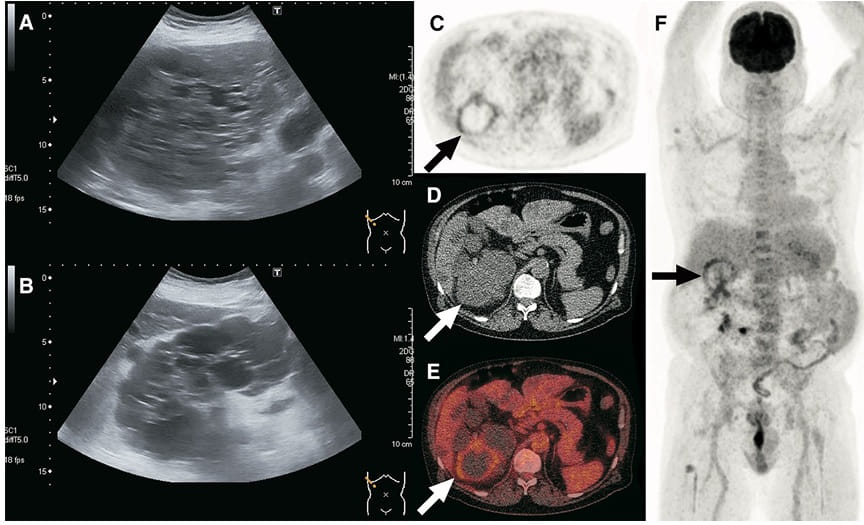

O 18F-FDG PET/CT surge como ferramenta de maior especificidade, útil para localizar o(s) cisto(s) infectado(s) e definir o alvo da punção.

Entretanto, a KDIGO ressalta que o PET/CT não deve ser exame de rotina, devendo ser reservado para casos selecionados, quando os métodos convencionais não esclarecem o diagnóstico.

📚 Na série de casos da imagem abaixo (**[link](https://link.springer.com/article/10.1007/s40336-017-0261-8)**), é possível ver como o PET/CT-FDG orienta a conduta e modifica o manejo em infecções renais e hepáticas na DRPAD.